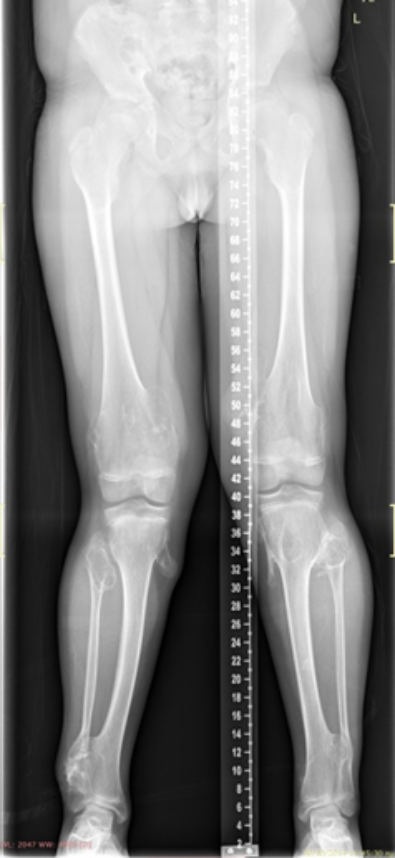

The images show a case of multiple osteochondroma which was operated by

Dr. Zenios in order to restore the mechanical axis.

Pre-operative